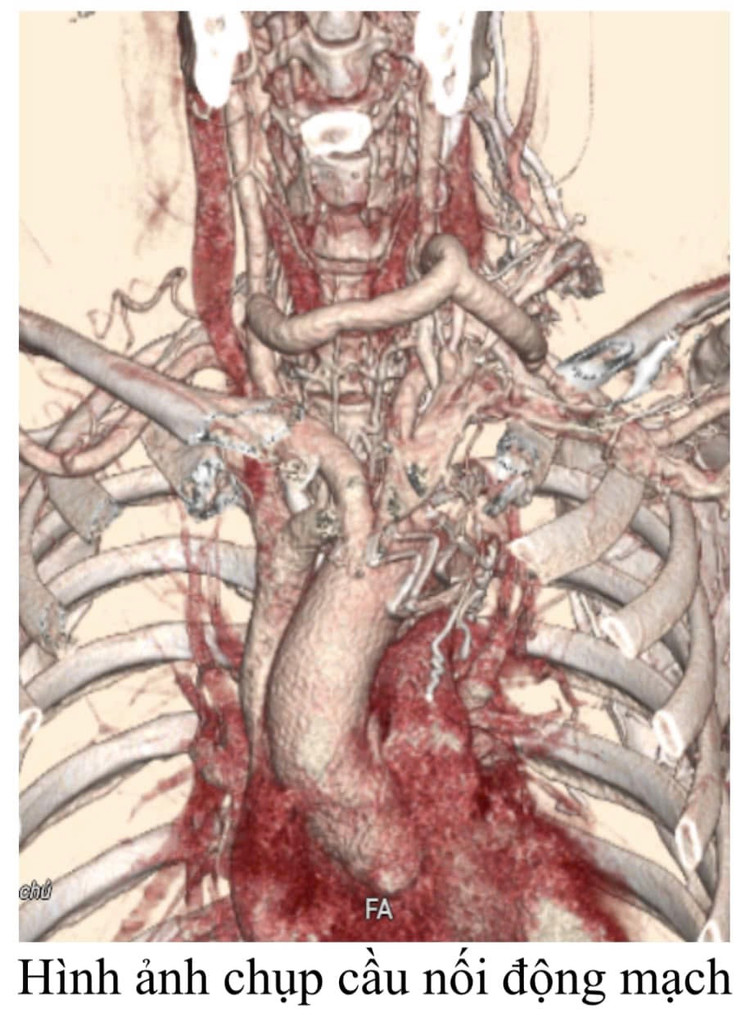

Trước tình trạng “ngàn cân treo sợi tóc” của bệnh nhân, các bác sĩ khoa Nội Tim mạch và khoa Phẫu thuật Thần kinh – Lồng ngực đã tiến hành hội chẩn khẩn cấp để đưa ra phương án điều trị cho người bệnh. Phương án tối ưu nhất được lựa chọn là phẫu thuật nối động mạch cảnh – cảnh, động mạch cảnh – dưới đòn trái để mở rộng vị trí đặt Stent Graft sau đấy sẽ tiến hành đặt Stent Graft.

Chỉ trong vòng 1 giờ sau hội chẩn, ê-kíp phẫu thuật mạch máu đã khẩn trương tiến hành phẫu thuật bắc cầu động mạch thành công.